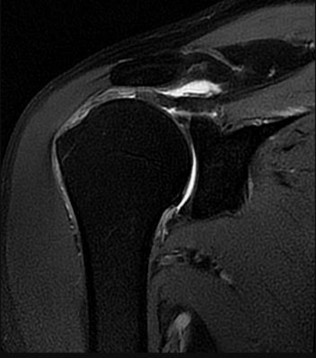

Orthopedic MCQS online Shoulder and Elbow 017 SHOULDER AND ELBOW SELF- SCORED SELF-ASSESSMENT EXAMINATION AAO…

ORTHOPEDIC MCQS ONLINE 014 UPPER EXTREMITY Shoulder and Elbow Self-Assessment Examination AAOS 2014 by Dr.Dha…